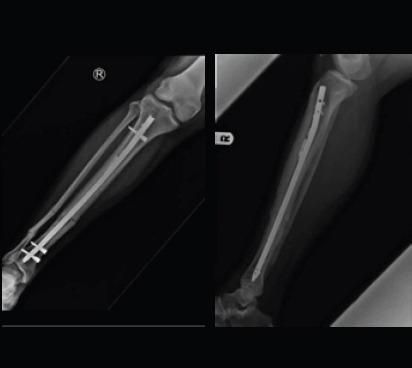

A 26-year-old male patient had road traffic accident and sustained a close fracture of the right distal 3rd tibia along with segmental fracture of the adjacent fibula. The tibia nailing was done under combined spinal and epidural anesthesia. The proximal tibia was approached by a midline incision with splitting of the patellar tendon. The reduction of the fracture fragments was done and the guide wire was inserted. The medullary canal was narrow and hence the initial reaming was started with the smallest available, that is, 8 mm reamer. After crossing the fracture site, we noticed that reamer coiled shaft got broken into multiple pieces in the medullary cavity at proximal 3rd tibia. The fracture site was exposed and a linear osteotomy was done in distal tibial fragment. Through this window, the broken reamer was pushed in the retrograde manner and was delivered out. Most of the broken metal pieces of the reamer shaft were removed with pituitary rongeur. An 8 mm solid IM nail was passed in antegrade manner across the fracture site and was locked distally and proximally. The operative wounds were irrigated and closure was done in layers. The patient was allowed partial weight bearing at 3 weeks post-surgery with gradually progressing to full weight bearing at 10 weeks after confirming clinical and radiological union.

一名26岁男性患者遭遇道路交通事故,导致右胫骨远端三分之一处闭合性骨折,同时相邻腓骨出现节段性骨折。在腰麻联合硬膜外麻醉下进行胫骨钉固定。经髌腱正中切口显露胫骨近端。对骨折碎片进行复位并插入导丝。髓腔狭窄,因此最初使用最小号的扩孔钻,即8毫米扩孔钻开始扩孔。穿过骨折部位后,我们注意到扩孔钻的螺旋轴在胫骨近端三分之一的髓腔内断成多段。显露骨折部位,在胫骨远端碎片上进行线性截骨。通过这个窗口,将断裂的扩孔钻逆行推挤并取出。用咬骨钳取出了扩孔钻轴的大部分断裂金属碎片。一枚8毫米实心髓内钉顺行穿过骨折部位,并在远近端锁定。冲洗手术伤口并分层缝合。术后3周允许患者部分负重,在确认临床和影像学愈合后,逐渐在10周时过渡到完全负重。